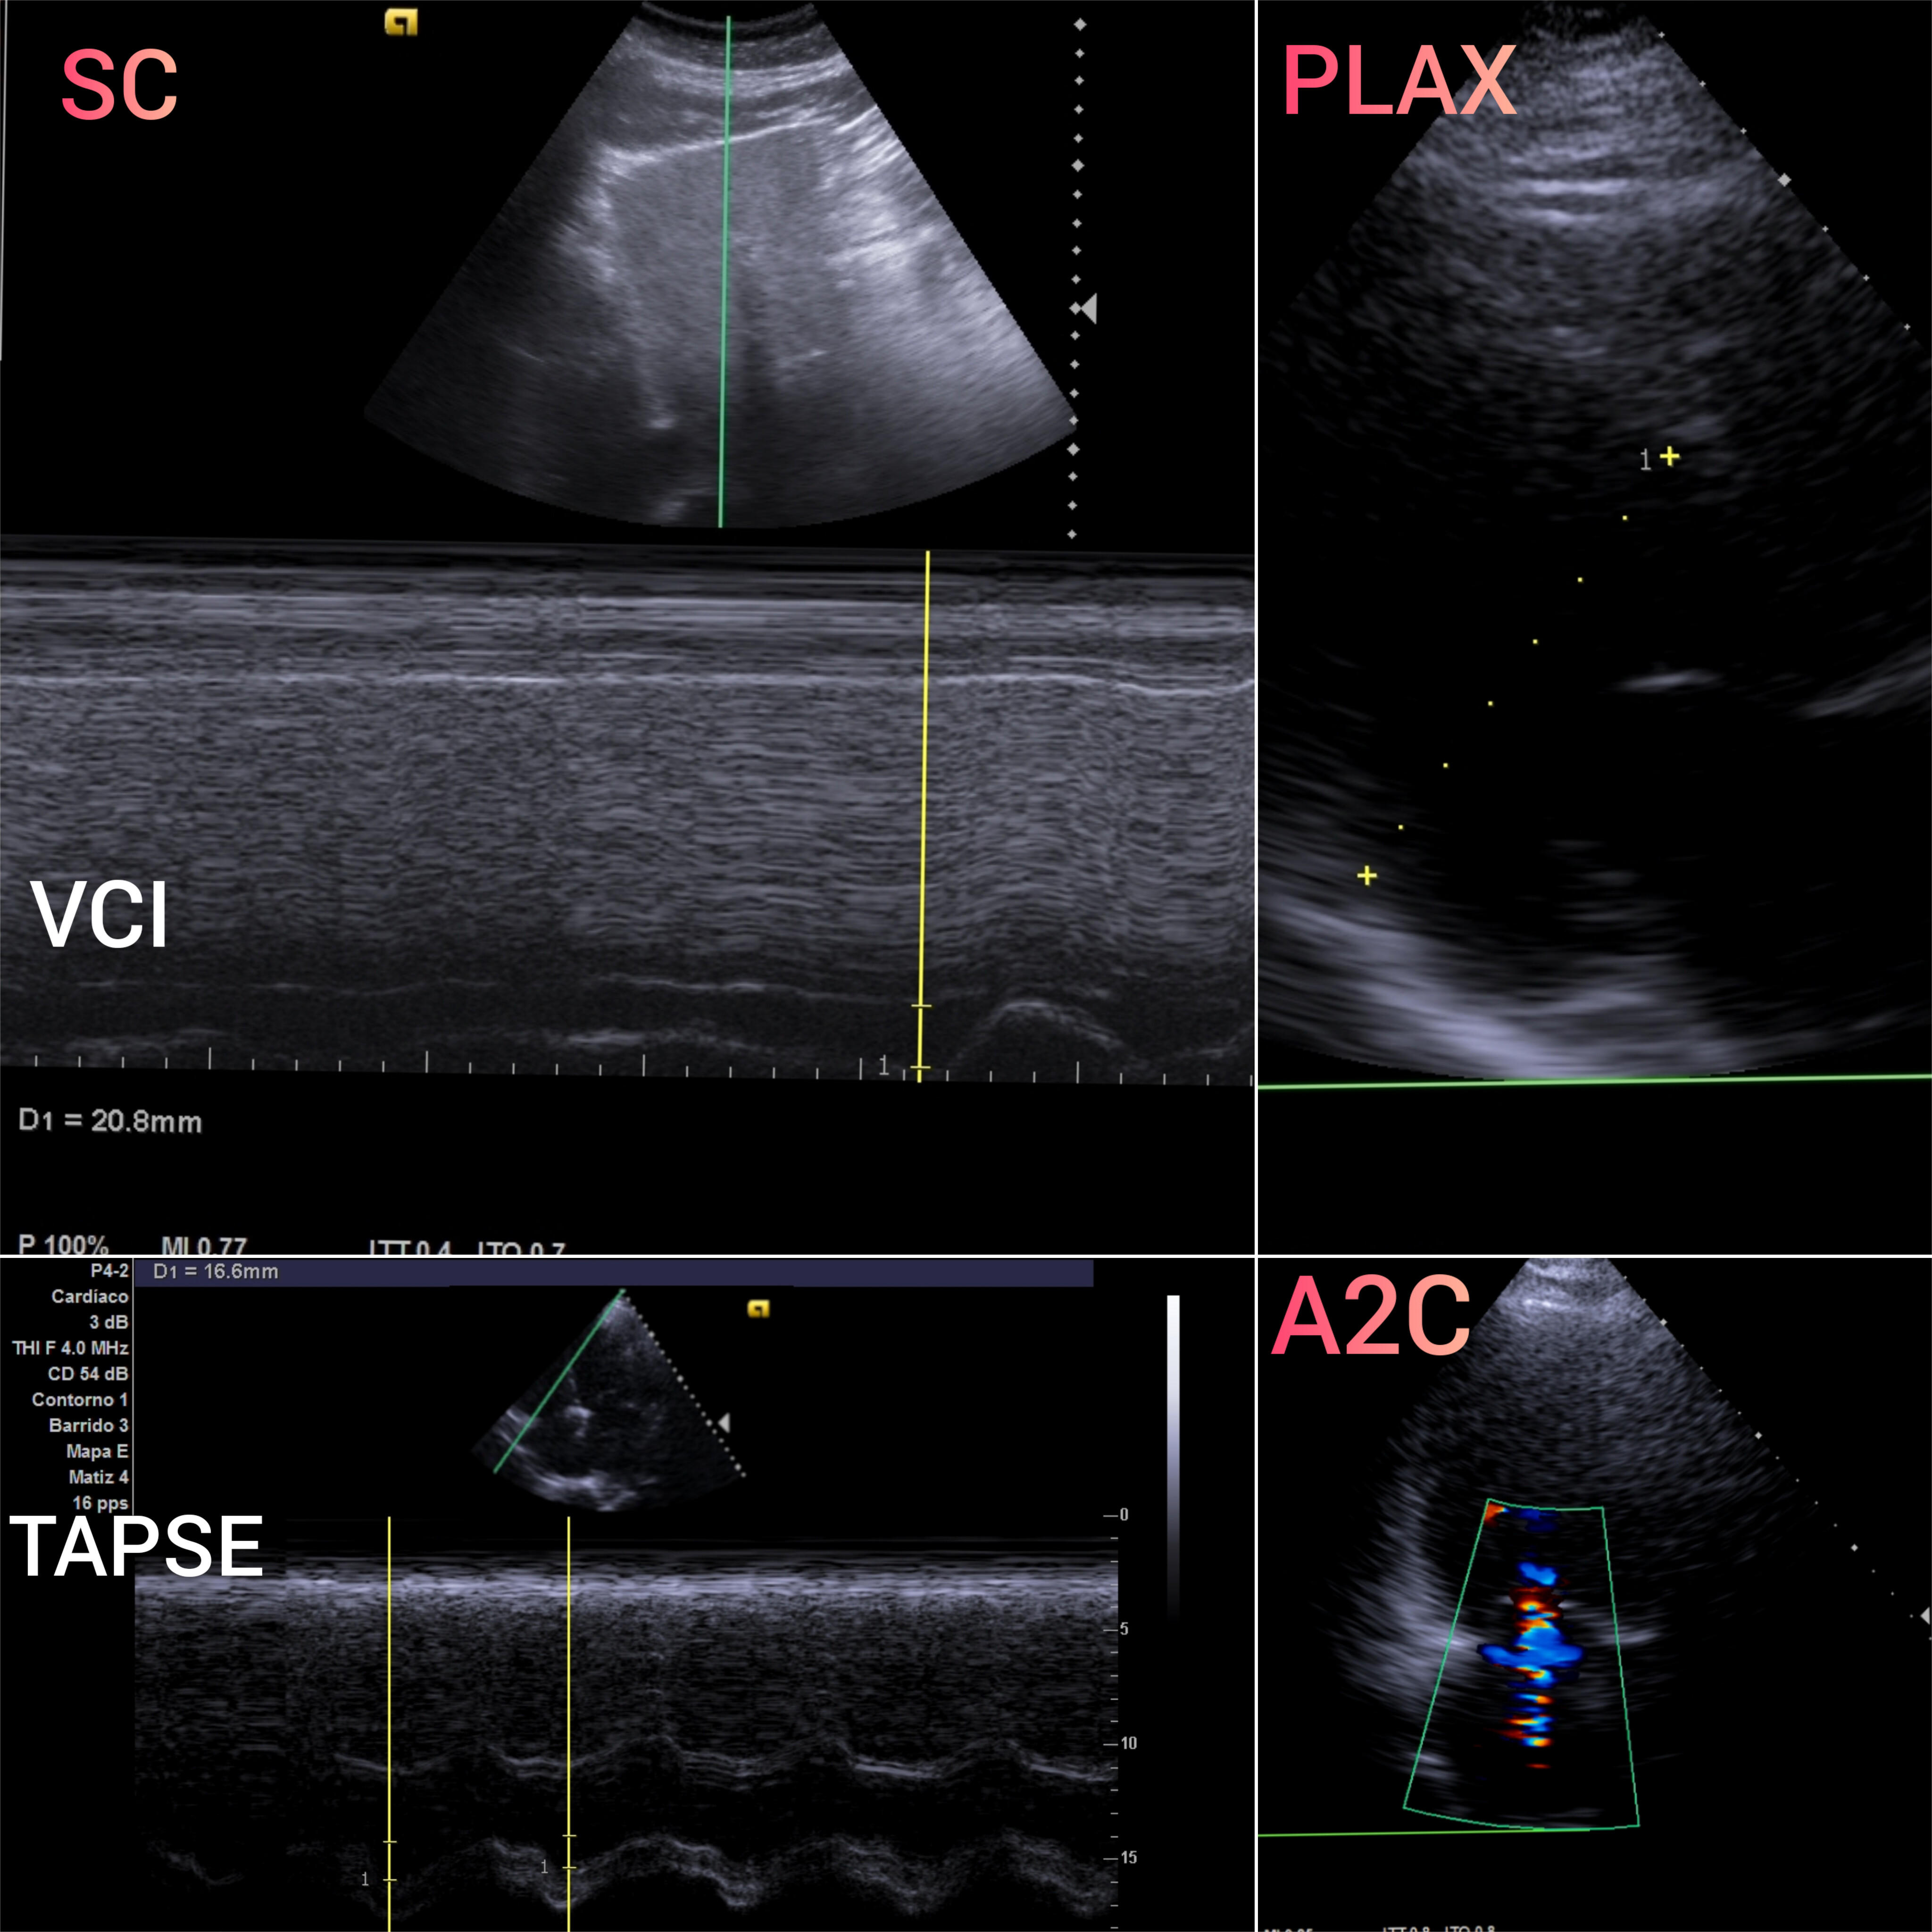

VEXUS: Vena cava inferior VCI 2,1 con colapsabilidad > 50%; Flujo portal y renal continuo.

EcoCardioscopia: Mejoría de contractilidad subjetivamente respecto a previo, cavidades izquierdas dilatatadas tanto VI como AI.